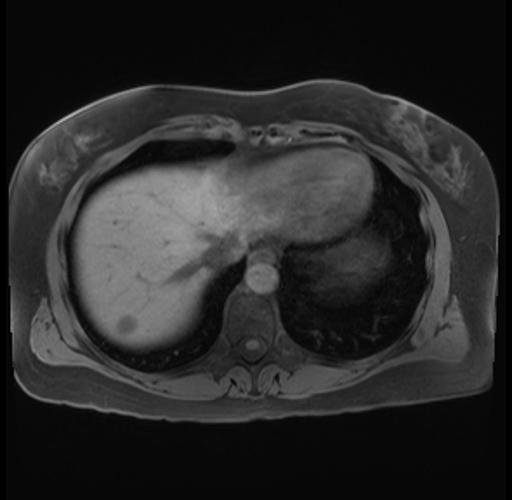

Imaging Analysis

Look through the patient's CT scan to identify any areas of concern for the necessary procedure.

Based on your CT findings, which issue(s) are present and would give reason for "planned slowing down moment(s)" in this case?